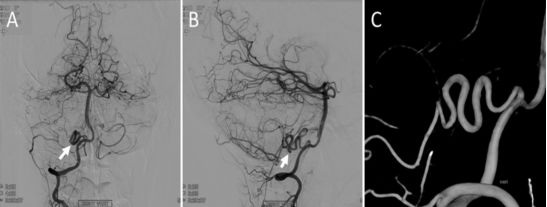

“纯动脉畸形”(pure arterial malformation,PAM)是指在没有动静脉分流的情况下,扩张、重叠和扭曲的动脉形成的线圈样外观的动脉环。这些病变的发病机制不清,被怀疑系先天性疾病。作者报告了1例17岁女性患者,因先兆偏头痛行头部MRI,偶然发现小脑后下动脉(PICA)近端PAM,其中有脂肪组织分布在动脉环内。随访8年,MRI均显示血管及脂肪组织结构稳定,DSA亦证实为PICA近端PAM。作者认为这种异常的颅内血管和脂肪组织间的关联进一步支持PAMs是先天性畸形的理论,考虑到其预想的良性自然病程,对该疾病行保守治疗是安全的。

![]()

经右侧椎动脉DSA造影显示小脑PICA近端PAM:正位片(A) ,侧位片(B),3D旋转成像(C)。